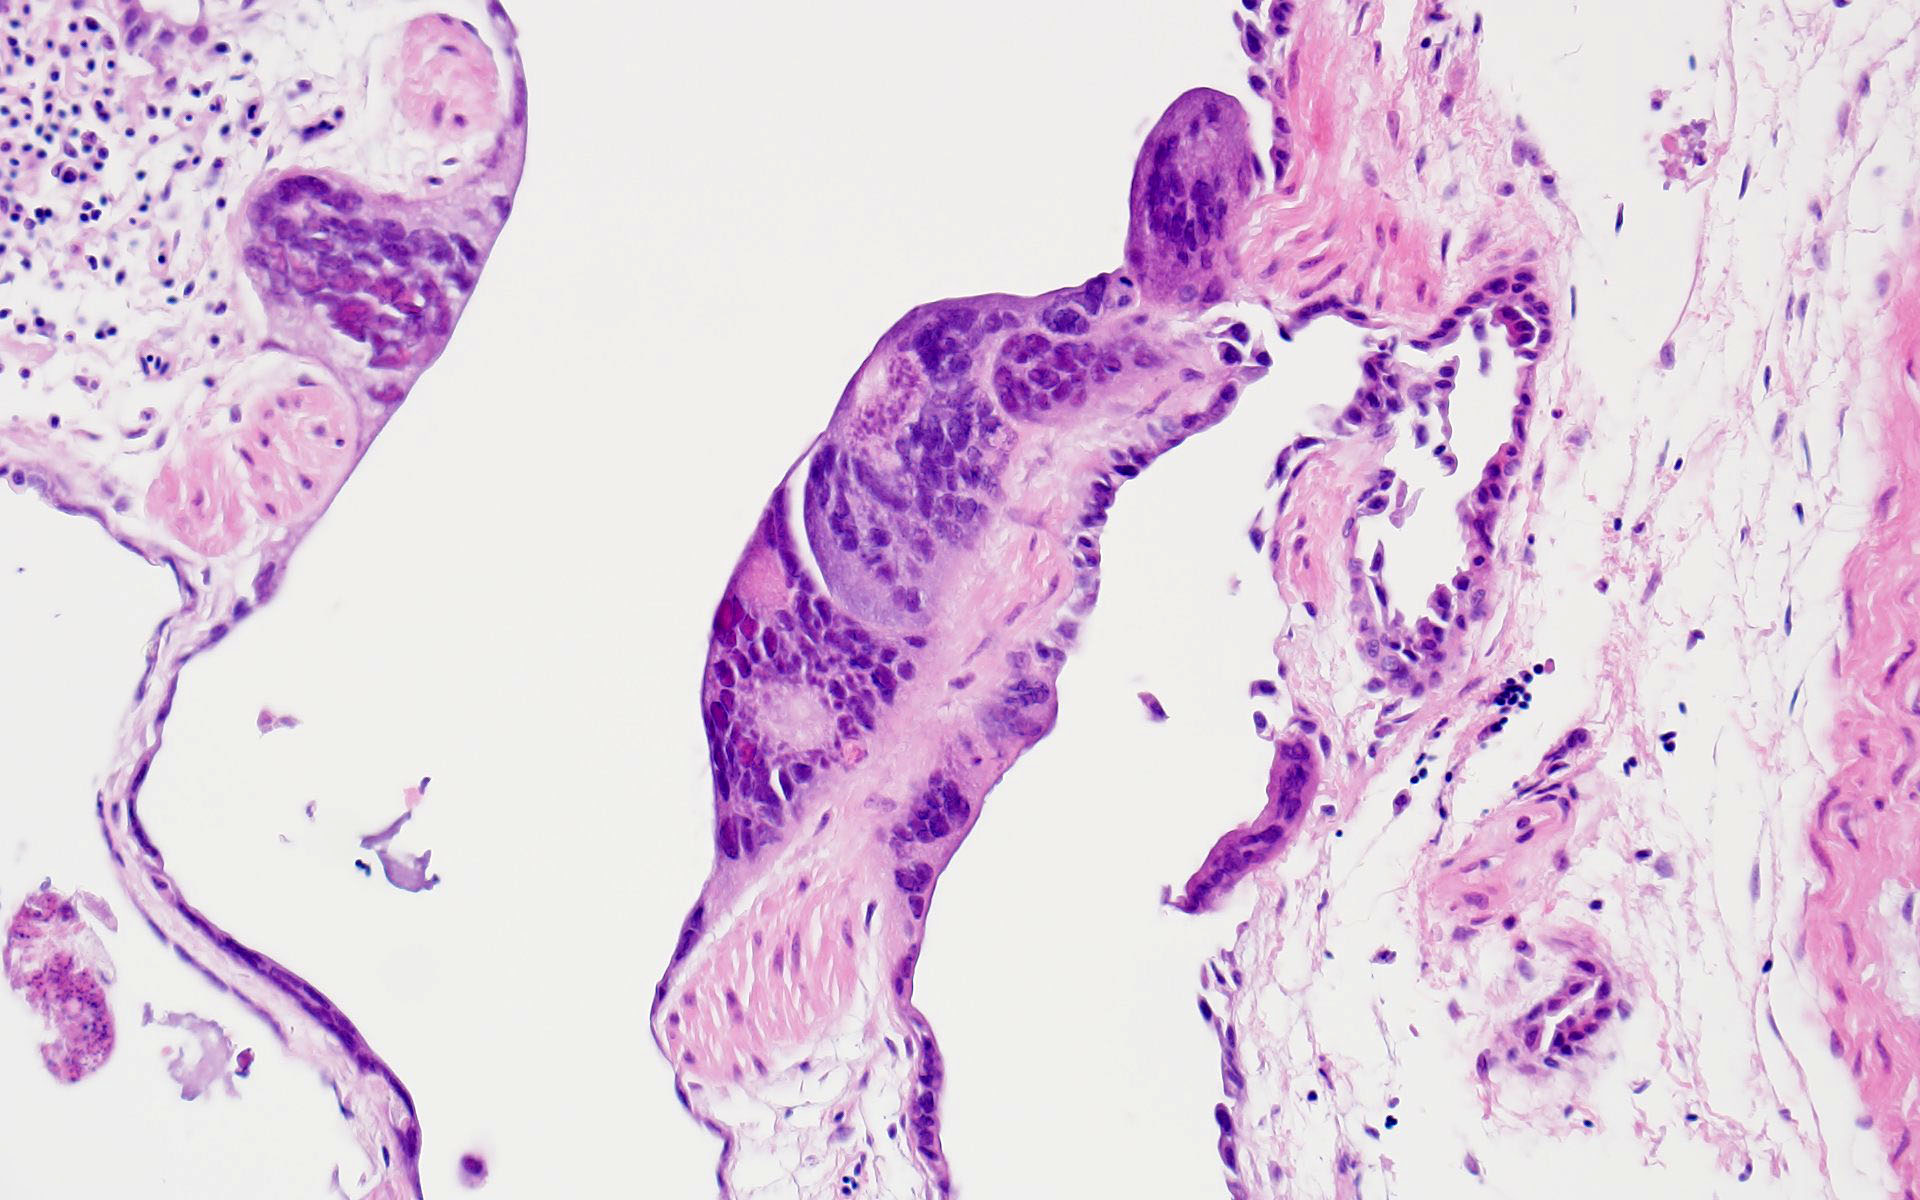

Microscopic Description:

The bronchi and parabronchi contain numerous large syncytia with large amphophilic-to-eosinophilic intranuclear inclusions that marginalize the chromatin. Bronchi and parabronchi also often contain foamy macrophages, pale basophilic mucus, homogeneously eosinophilic edema fluid, fibrin, cellular debris, and sloughed necrotic epithelial cells.

- Tubular reproductive tract, air sac, lung: Epithelial necrosis, acute, multifocal, moderate, with intranuclear viral inclusions and numerous syncytia.

The JPC’s own Dr. Elise LaDouceur moder-ated this year’s avian-focused seventeenth conference. This first case provided participants with a panoply/salmagundi/”dog’s breakfast” of tissues to sort through to achieve a diagnosis. The characteristic intranuclear viral inclusion bodies of herpesvirus were best seen in the air sac respiratory epithelium, which also rewarded conference-goers with some exceptional viral syncytia. Of the potential herpesviral culprits, psittacine al-phaherpesviruses (PsAHV) 1, 3, and 5 have been reported in psittacine species, including Indian ringneck parakeets, and PsAHV-5 was isolated by the contributor in this case. The contributor provided some beautiful electron microscopy (EM) photos from this bird that demonstrated intranuclear herpesviral virions, with some virions budding from the nuclear envelope to become enveloped themselves, and others hanging around the rough endo-plasmic reticulum (RER) to acquire additional proteins. The JPC is grateful to the contributor for providing these excellent educational images!

In addition to the respiratory epithelium, a tubular structure adjacent to the ovary was also affected by PsAHV-5 (i.e., had syncytia and epithelial necrosis). The smooth muscle wall and cellularity of this structure is consistent with either oviduct or remnant Wolffian duct. This suggests that PsAHV-5 may have a broader epitheliotropism beyond respiratory epithelium.